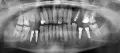

Подскажите, пожалуйста, можно ли по панорамному снимку определить правильность установки импланта? Имплант устанавливался на место шестерки, верхней челюсти, закрытый синус-лифтинг, с 1 гр. кости. Сколько по норме миллиметров должно быть между корнем зуба и имплантом? Является ли нормой, что после снятия швов, языком нащупывалась точка импланта, а вскрытие было бескровное?

В вашем случае поврежден корень зуба и необходимо срочно извлечь имплантат. Ответы на другие вопросы не актуальны. Это, что касается нижнего имплантата. На верхней челюсти я не вижу качественной операции, закрытый синус, так как имеется перфорация на 2 мм. пазухи. Рекомендую обратиться к хирургу.